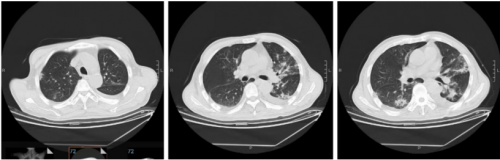

10月26日复查肺ct略有吸收,局部形成空腔。少量胸腔积液。

10.26肺ct